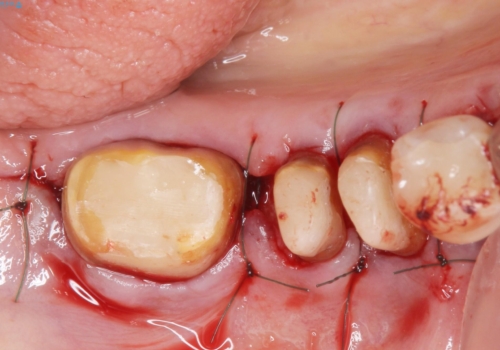

- 歯ぐきからの出血と腫れを主訴に来院された患者様です。

プラークコントロールが非常に悪く、全顎的な歯周病に罹患していました。

「抜歯したくない、インプラントは嫌」という患者様のご希望とご年齢を考慮し、可及的な骨外科処置や根分割術によりできるだけ今ある歯を残す治療方針をたてました。

保存不可能な左上の奥歯2本(左上67)は抜去し、ノンクラスプデンチャーをいれることにしました。

長期的な予後は保証できないことをご了承頂いた上で治療を行いました。